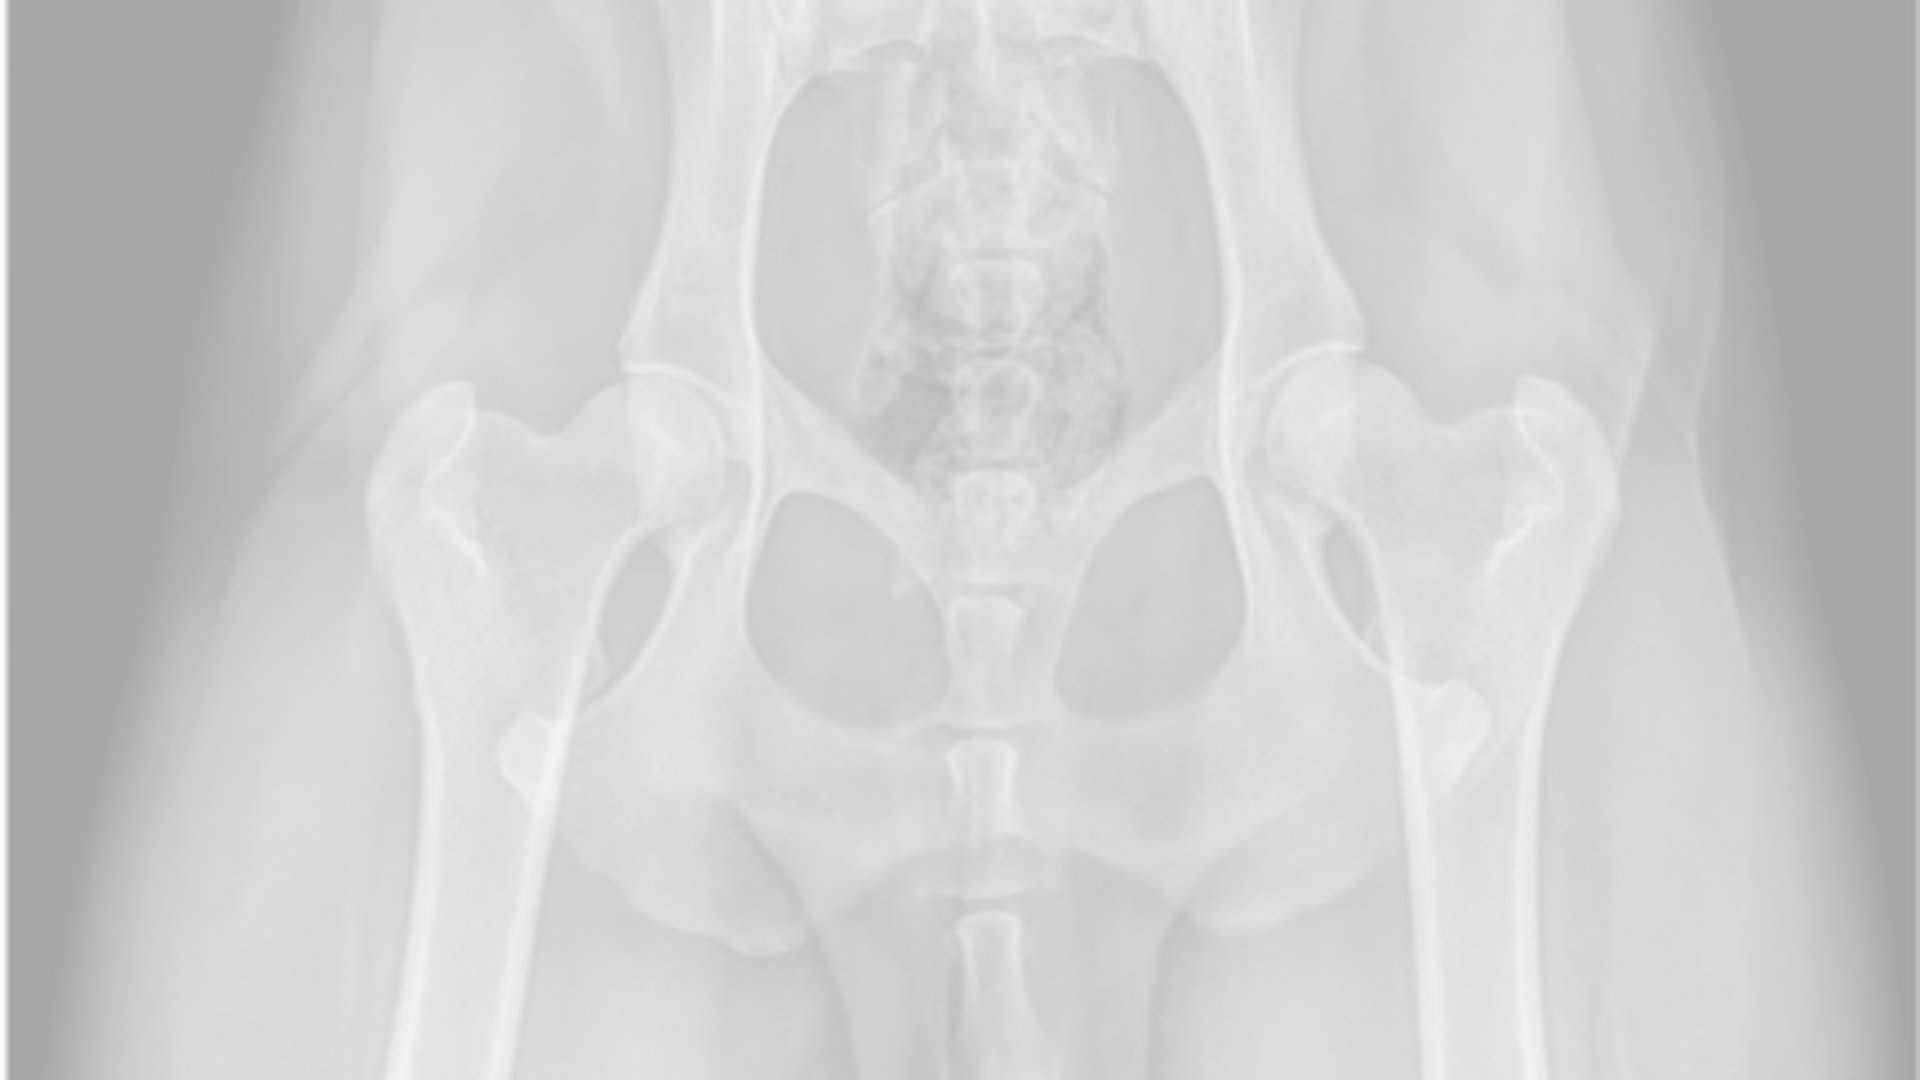

Hip Dysplasia Scheme

This is carried out under deep sedation or general anaesthetic and can be done at your own veterinary surgery or a centre that specialises in doing them. The radiographs then have to be sent away to be scored at the BVA or another body such as the Australian panel. The hips can be X-rayed once the dog is over 1 year of age.

The hips are scored individually with the best hips being 0/0 and the worse 53/53 total 106.

The median score for Goldens at present is 11 in total for both hips and BVA recommend breeding close to that score. Both parents should be scored, as well as all grandparents at the very minimum.